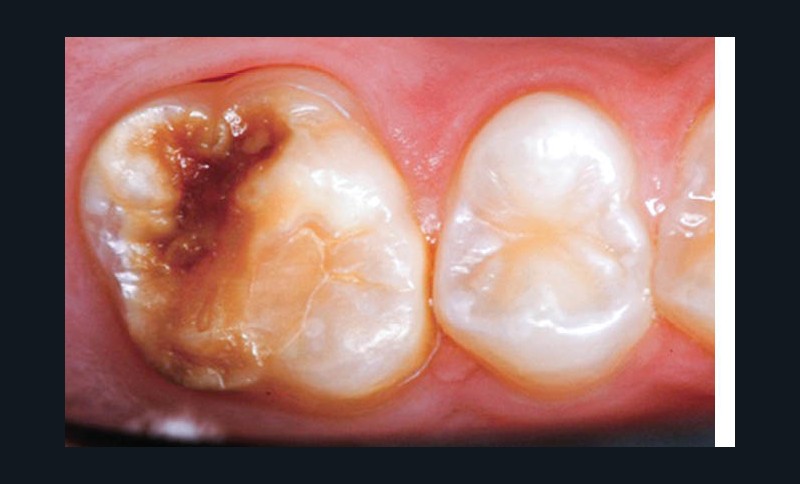

L’émail dentaire, tissu le plus dur et le plus minéralisé du corps humain, peut être affecté par des anomalies génétiques inscrites dans le génome de l’individu, mais également par des facteurs environnementaux. Ces facteurs sont multiples et signent un événement ou une exposition à un xénobiotique au cours de la vie de l’individu. Parmi les atteintes développementales acquises de l’émail, outre la fluorose, figurent les hypominéralisations à type de MIH (Molar Incisor Hypomineralization). Celles-ci sont observées de manière caractéristique sur une ou plusieurs premières molaires permanentes et potentiellement les incisives permanentes éruptant vers l’âge de 6 à 7 ans d’après la description qui en a été faite en 2001 [3] (fig. 1 à 3). La prévalence est importante, la MIH touchant, selon les méta-analyses les plus récentes, plus de 13 % des individus dans le monde, et peut varier selon les études et les pays dans lesquels elles sont menées [4, 5]. Son étiologie est encore incertaine, mais la communauté scientifique s’accorde sur le fait qu’elle serait multifactorielle et notamment en lien avec la survenue d’une hypoxie à la naissance, de fortes fièvres, des épisodes infectieux de la sphère ORL dans la petite enfance ou encore avec une prédisposition génétique [6]. Cette pathologie aurait toujours existé, mais sa prévalence semble être en nette augmentation. Peu d’études ont été réalisées sur cette évolution dans le temps [7].

Les cellules responsables de la synthèse de l’émail, les améloblastes, disparaissant au moment de l’éruption des dents, les défauts de structure et de qualité de l’émail sont irréversibles. L’émail dentaire est ainsi capable d’enregistrer des événements environnementaux ayant eu lieu lors de sa formation. Ces défauts sont donc en quelque sorte le disque dur des contaminations que les améloblastes ont subies. De ce fait, le défaut de minéralisation caractérisant le MIH est le signe d’une exposition environnementale délétère intervenue au cours de la période périnatale (période d’amélogenèse des dents impactées par le MIH), soit environ 5 ans avant leur éruption (fig. 4).

Les leviers à activer dès maintenant pour répondre aux enjeux de santé publique liés à la MIH sont nombreux. C’est d’abord le développement de la collaboration avec les professionnels de santé de la petite enfance. Ceux-ci, dont les médecins généralistes, doivent être sensibilisés au tableau clinique de la MIH – différent de celui de la fluorose ou de l’amélogenèse imparfaite par son caractère asymétrique et sa localisation préférentielle aux molaires et incisives permanentes – afin de favoriser son dépistage et sa prise en charge précoce.